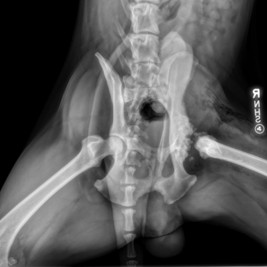

2026 had just begun when Kairo, a 3-yr-old hound mix, was found as an injured stray. @NEHumaneSociety vets performed FHO (femoral head ostectomy) surgery. He is currently healing in foster care and receiving check-ups with NHS vets. Once recovered will be ready for home.